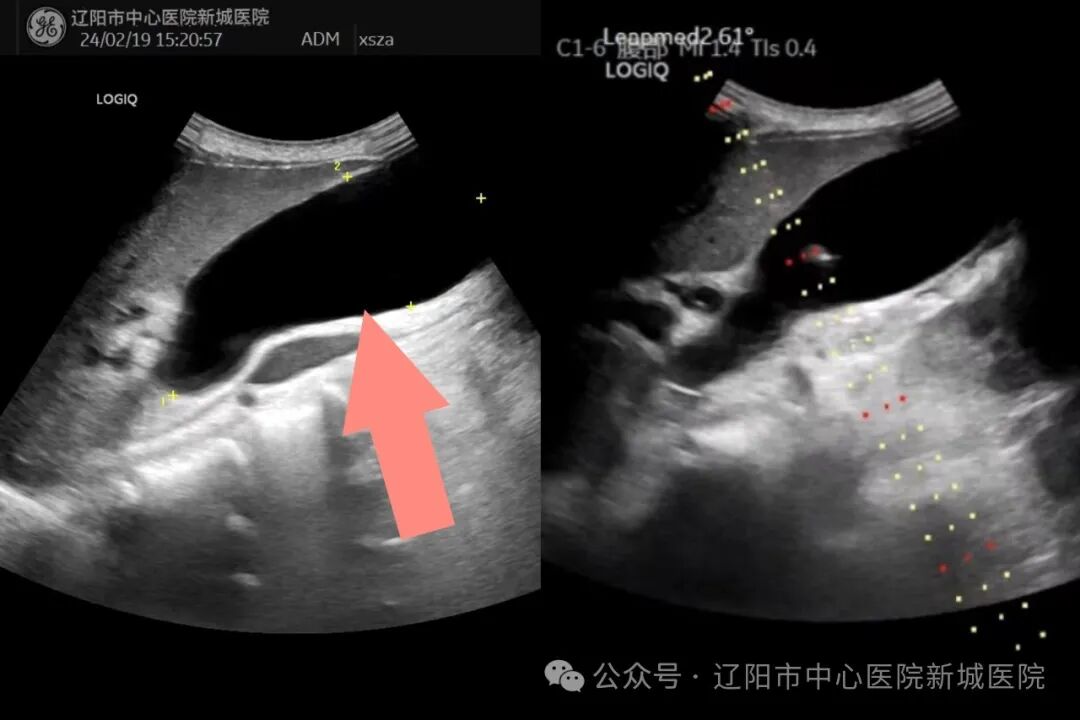

肝内胆管扩张

两位主任认真询问老人病史,结合磁共振和CT的检查结果,为老人进行细致的超声检查,进行精准诊断;并邀请了院内多位学科专家进行会诊,综合评估老人的病情,决定为老人进行超声引导下行经皮肝穿刺胆管引流术、经皮肝穿刺胆囊引流术,解除胆道双梗阻,提高生活质量。

张雅丽主任和刚玉恩主任共同为老人分步进行微创手术:首先采用超声引导下行经皮肝穿刺胆管引流术,穿刺针进入胆管,抽出白色透明胆汁100ml,超声显示左右肝内胆管扩张明显缓解,解决老人的肝内胆管扩张问题。然后采用经皮肝穿刺胆囊引流术,抽取胆汁120ml,超声显示胆囊明显缩小,解决了胆囊内胆汁潴留问题。术中老人没有不适感觉,术后安返病房,家属非常感谢两位主任给予的救治。老人于术后次日即康复出院。